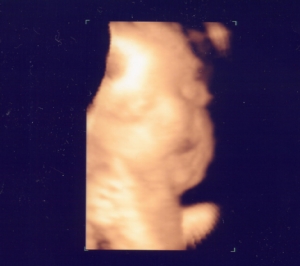

32週目、月数では9ヶ月になります。

超音波は、赤ちゃん顔が子宮壁にくっついててちゃんとしたのが撮れなかった(^_^;)